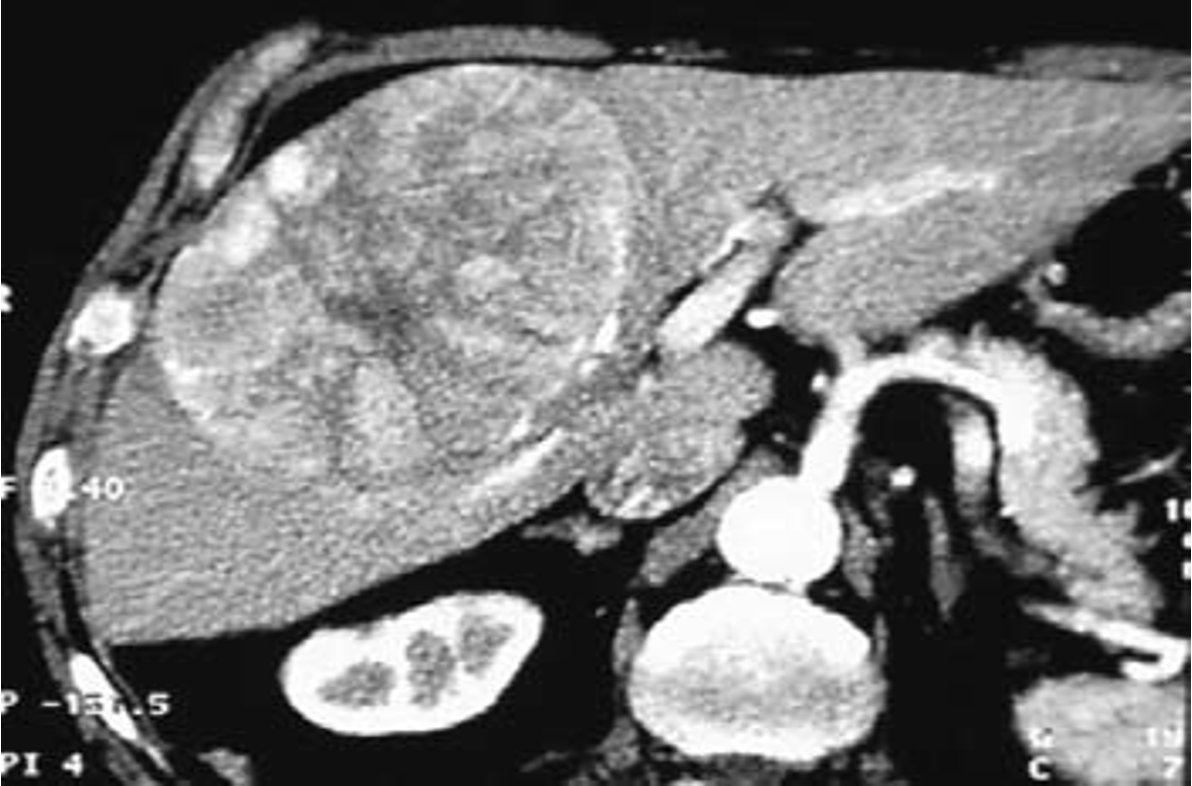

Imaging: Ultrasound, CT scan and MRI can assess the site, size, diagnosis of the tumor and can help in planning the surgical resection. CT scan will show hypervascular tumor.

HCC CT FINDINGS

Arterial phase shows hypervascularity of the HCC tumor on right lobe - washing in

in venous its opposite - washing out

diagnostic for HCC gold standard- doesnt need biopsy

irregular margin, liver shrink, ascites present

CT scan : Huge hepatocellular carcinoma in the right lobe of the liver